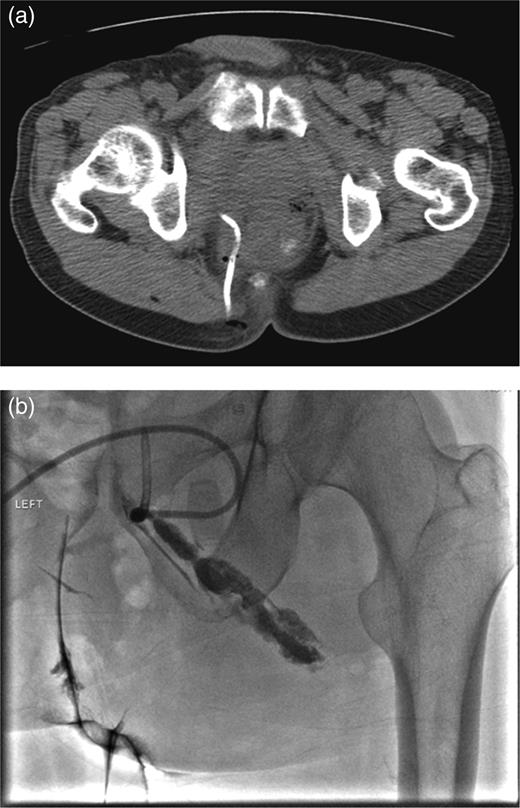

Contrast-enhanced computed tomography (CT) scan revealed the presence of diverticulosis and perirectal mesenteric stranding concerning for diverticulitis (Fig. 1); therefore, the patient was admitted and treated empirically for the same with i.v. antibiotics. He was discharged several days later with a 2-week course of amoxicillin clavulanate.

CT scan depicting perirectal stranding without definite abscess formation.